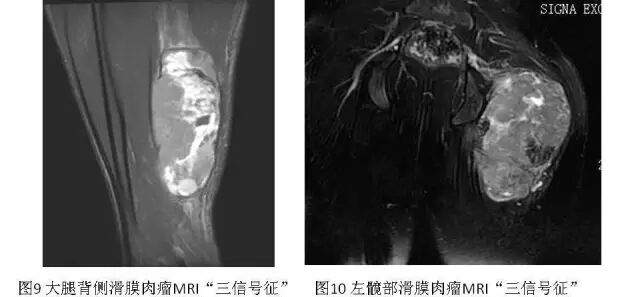

3.MRI

肿瘤在MRI上平扫表现为类圆形或分叶状肿块,T1WI信号多与肌肉相似,肿瘤合并出血时可出现小斑片状高信号区。少数因瘤内广泛的出血,整个肿瘤可呈高信号。T2WI上信号多不均匀,肿瘤内常出现高、等、低三种信号混合存在的征象,有学者称之“三信号征”(也有学者称之“三重信号征”或“三联征”)(图9、图10),是滑膜肉瘤MRI较为特征性征象之一。T2WI抑脂序列上滑膜肉瘤可呈多个大小近似的卵石状结节,其间存在低信号间隔,似铺路石状,称之为“铺路石征”(也有学者称之“卵石征”)(图11),也是滑膜肉瘤MRI较为特征性征象之一。部分病例(15%~25%)可出现液-液平面,为非特异性表现。常规MR增强扫描,肿瘤呈片絮状明显不均匀强化,分隔可呈明显强化(图11)。